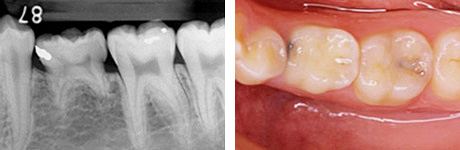

治療前の写真は乳歯がまだ残っています。

移植直後。